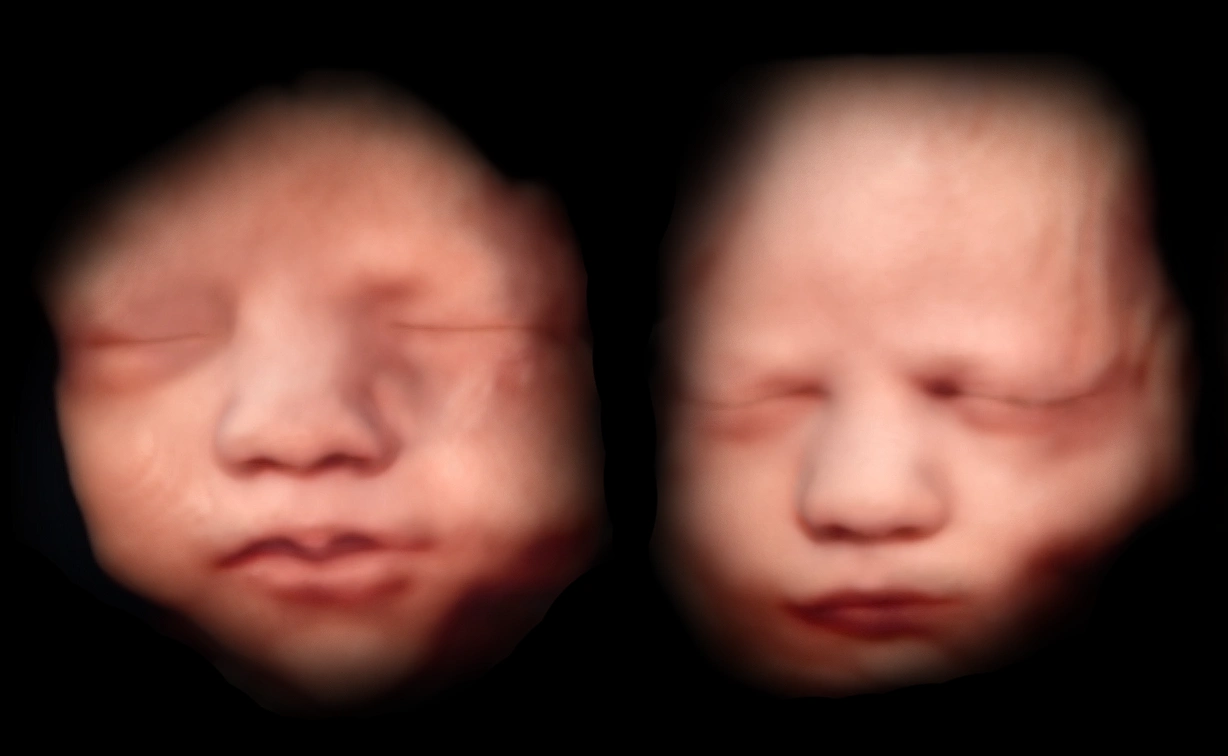

Ultraschalluntersuchungen (2D/3D/4D)

Durch regelmäßige Ultraschalluntersuchungen können wir die Entwicklung Ihres Babys überwachen und frühzeitig Auffälligkeiten erkennen.